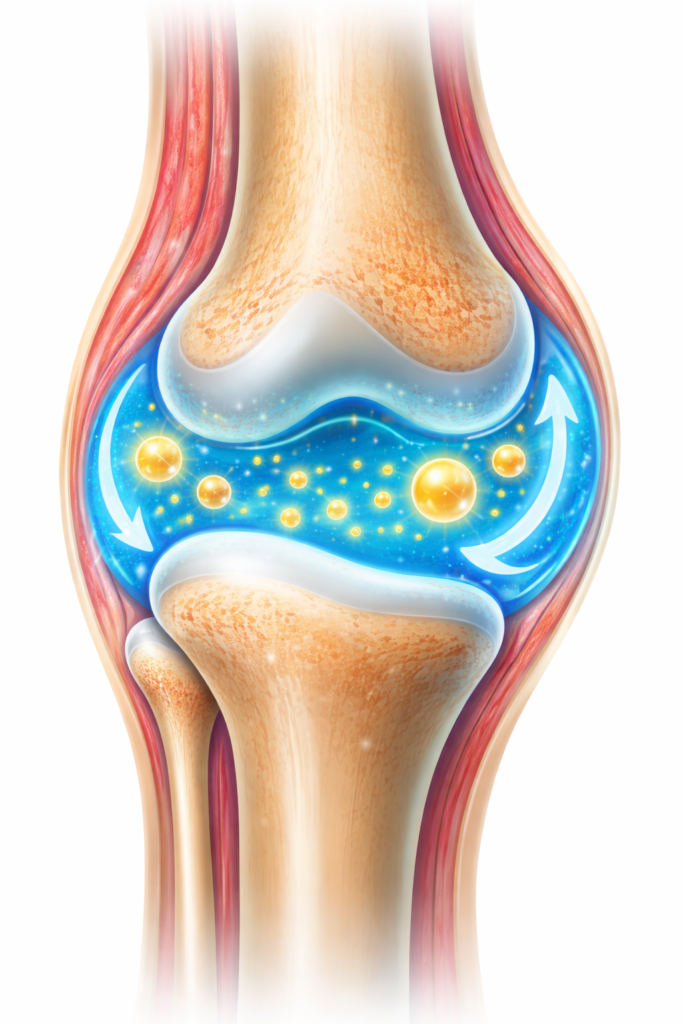

How Joint Genesis Works

Most joint products focus on inflammation only.

Joint Genesis takes a different path.

It targets synovial fluid.

This fluid acts like oil for your joints.

Low fluid means stiffness and pain.

Joint Genesis supports this fluid naturally.

Better fluid means smoother movement.

Less friction.

More comfort.